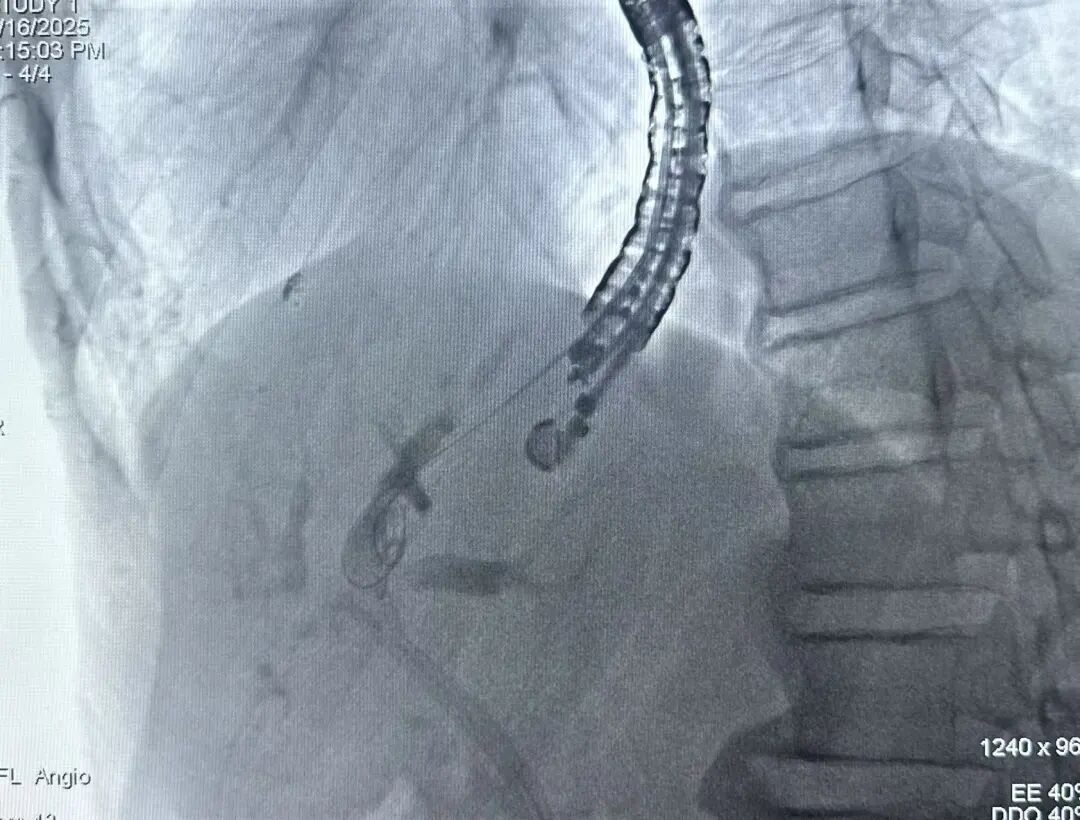

经全面评估及精心术前准备后,刘哲副主任首先在超声内镜引导下精准避开周围血管,找到最佳穿刺点后,将穿刺针经过胃壁穿刺进入肝内胆管,在超声和X线的双重辅助下,顺利留置导丝,随后对穿刺点进行切开、扩张、支架置入。手术不到1小时,不仅顺利地解决了胆道梗阻问题,还避免了外引流引起的胆汁丢失、感染、生活质量下降等问题。术后患者黄疸症状明显改善,食欲逐渐恢复,生活质量得到显著提升。

EUS-BD-HGS是一种先进的微创手术,是目前国内外内镜操作技术领先的高水平代表,具有创伤性小、成功率高和并发症少的优点。通过在超声内镜的引导下,在贲门或胃体小弯侧扫查肝内胆管情况,确定目标胆管后,经胃经肝穿刺肝内胆管,然后放置导丝,并沿导丝放置胆道支架,从而使胆汁通过支架引流至胃腔。